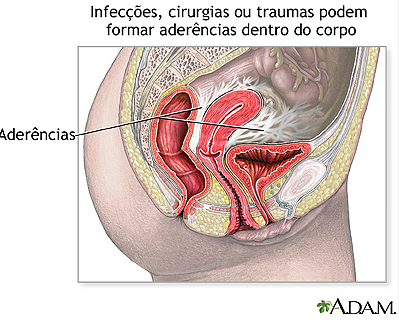

Nós, fisioterapeutas que trabalhamos com terapia manual e osteopatia, entendemos que em muitos casos a origem da dor ciática pode estar relacionada a congestões, tensões e aderências nas vísceras (órgãos internos).

Essas vísceras são envolvidas por tecidos chamados fáscias, que fazem conexão com músculos, nervos e articulações. Quando essas fáscias perdem mobilidade, podem gerar tensão à distância.

Disfunções nessas áreas podem aumentar a tensão mecânica no corpo e irritar o trajeto do nervo ciático, resultando em dor, formigamento ou sensação de peso na perna.e nessas regiões podem gerar sobrecarga e irritação do nervo ciático.